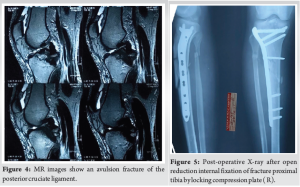

A 34-year-old male was admitted to the emergency department at S N Medical College, Agra, as a case of comminuted fracture proximal tibia and fibula (R) with ipsilateral avulsion fracture of PCL (Fig. 1-4), due to motorcycle-motorcycle collision 3 days before the admission.

We planned to manage both fractures in a two-stage surgery. The selected approach involved open reduction internal fixation of fracture proximal tibia by LCP followed by open reduction and internal fixation of PCL avulsion using cannulated cancellous screws, supplemented by the innovative application of a spiked washer for enhanced stability. Post-operative X-ray after open reduction and internal fixation of the proximal tibial fracture with an LCP (R) (Fig. 5). The implant is appropriately aligned, with satisfactory reduction and fixation of the fracture fragments, ensuring stability for healing. The interval between the two surgeries was 10 days, allowing time for the skin incision to heal and the soft-tissue swelling to subside. Following the acquisition of informed consent, the patient was planned for ORIF using cannulated cancellous screws and spiked washer, employing the modified posterior approach as detailed by Burks and Schaffer [6]. The patient underwent surgery under spinal anesthesia. He was placed in a prone position on a radiolucent operating table, ensuring adequate padding for pressure points. The lower extremity was positioned with a 30° flexion at the knee joint, supported by a bolster at the ankle, and a pneumatic tourniquet was applied to the patient. An inverted “L”-shaped incision was performed, starting from the medial aspect of the gastrocnemius and curving along the joint’s flexor crease toward the lateral side (Fig. 6).